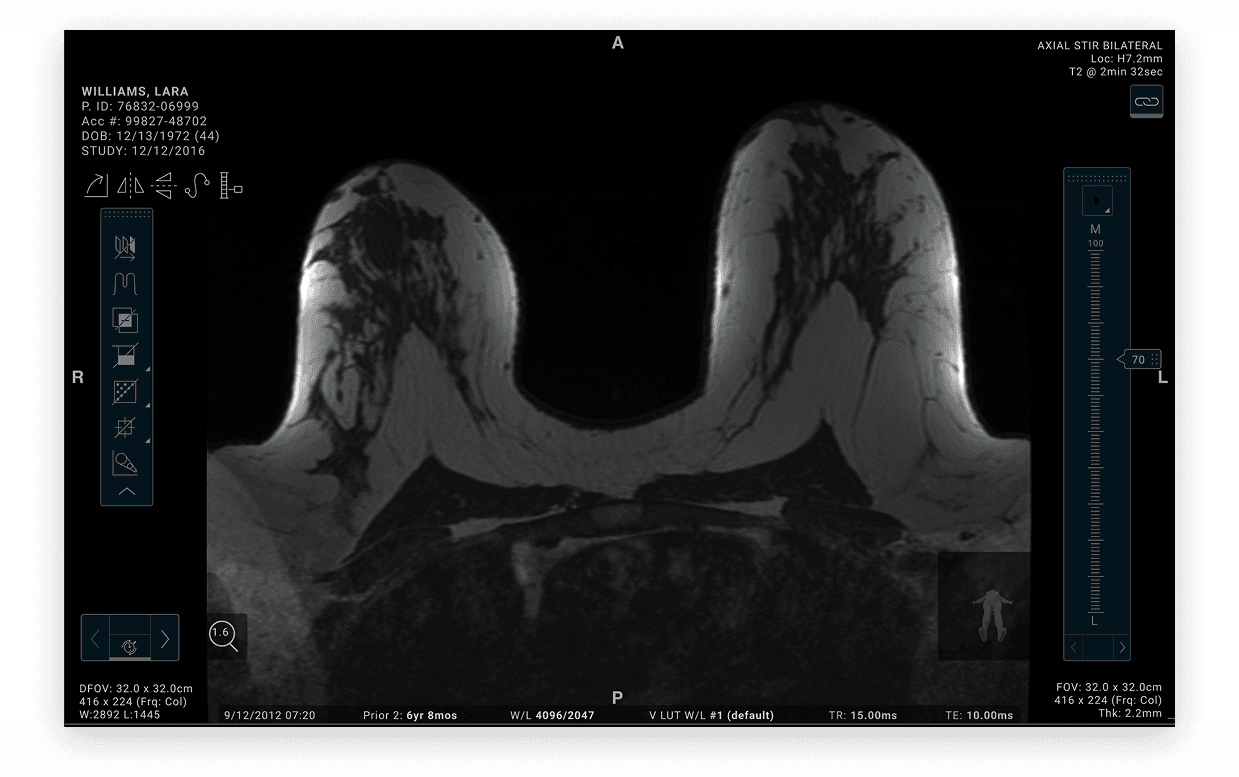

Clinical workflow transformation

Decluttering high-density MRI views for safer decision-making